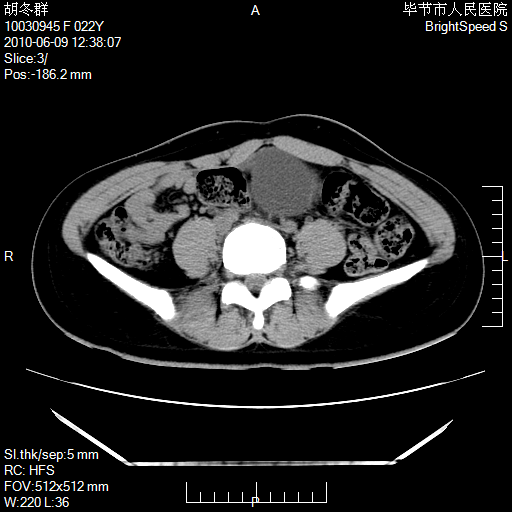

患者23岁,发现腹部包块3月。

盆腔内囊性占位;穿刺或者直接手术拿掉即可,不必紧张。

我当时考虑重复膀胱,但我错得很厉害,我不明白,囊肿排尿后为什么能到膀胱位置。

盆腔内囊性占位性病变;考虑左侧卵巢囊腺瘤。

有分隔、壁薄,支持考虑左侧卵巢囊腺瘤。

左侧卵巢浆液性囊腺瘤。

有分隔、壁薄,支持考虑左侧卵巢囊腺瘤。排尿后,膀胱缩小,由于重力作用,肿块下移就到了膀胱位置,很好理解。